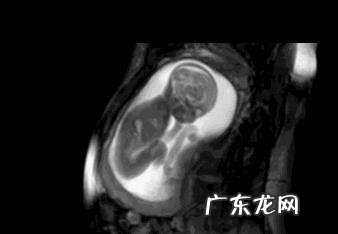

胎动无论是左边还是右边只要我们每次去做产检胎儿正常是没关系,怀孕5个月胎儿已经是比较成形了,马上就去照三维或者四维彩超了,妈妈就可以拿到妈妈一张比较清晰的相片了 。